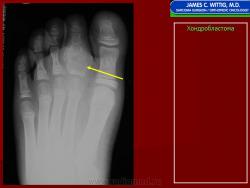

Рентгенологически хондробластома представляет собой сравнительно большой (2-4 см) очаг округлой формы, четко отграниченный от окружающей кости склеротической каймой. На фоне очага в большинстве случаев, но не обязательно определяются плотные включения, напоминающие хлопья ваты.

Рентгенологическая картина. Хондробластома выглядит как небольшой, от 3 до 6 см литический очаг, центрально или эксцентрично расположенный, с четкими контурами, занимающий около половины площади эпифизарной зоны. Хондробластома плоских костей и мелких трубчатых костей больших размеров, может сопровождаться припухлостью мягких тканей, вздутием кости и периостальной реакцией. Распространение процесса на метафизарную зону встречается часто.